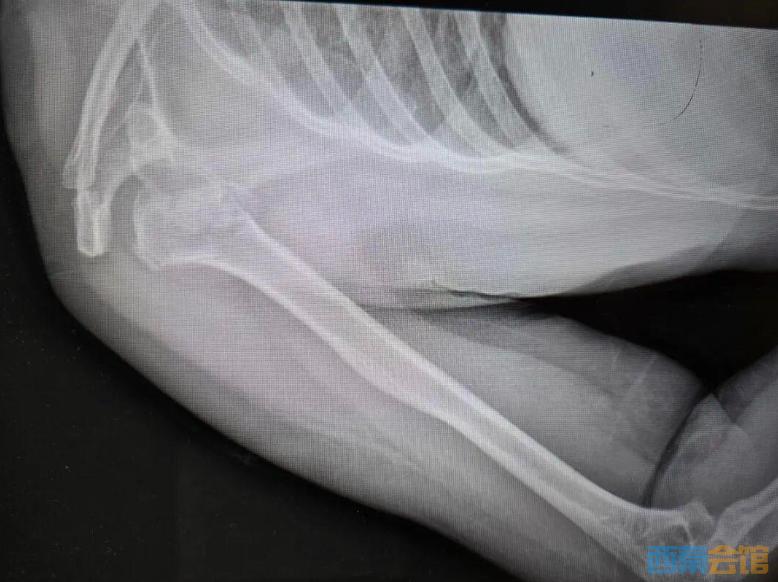

送医后的CT检查结果显示:右肱骨近端四部分粉碎性骨折,且伴有罕见的肱骨头后脱位。她的肩膀碎成了七八块,而且关节位置发生了严重偏移。由于手术难度极大,她被紧急转诊至河南省人民医院。